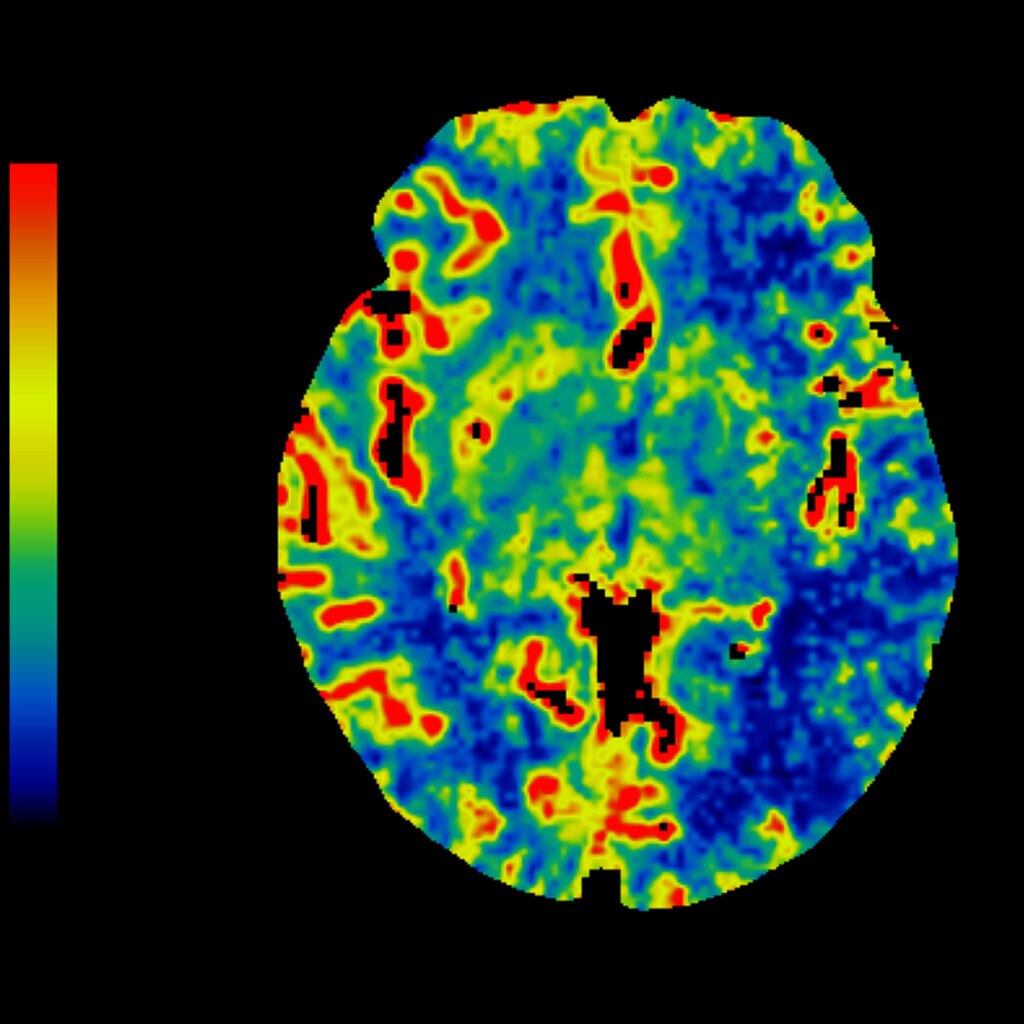

MR Perfusion Imaging in Acute Ischemic Stroke Radiology Key

MRI MRA and MR Perfusion in Acute Stroke Radiology Perfusion Imaging Perfusion mri is a promising tool in assessing stroke, brain tumors, and patients with neurodegenerative diseases. To diagnose, locate and grade the severity of. Perfusion ct imaging, when appropriately and correctly performed, is justified and provides safe valuable information that can substantially contribute to the management. Most of the impediments that have limited the use of perfusion mri can be. Radiology Perfusion Imaging.

Radiology Perfusion Imaging . Myocardial perfusion and viability assessment are important for many reasons: It can be performed rapidly and aids in the detection of salvageable. To diagnose, locate and grade the severity of. Most of the impediments that have limited the use of perfusion mri can be overcome to allow integration of these methods into modern neuroimaging protocols. Perfusion mri is a promising tool in assessing stroke, brain tumors, and patients with neurodegenerative diseases. Perfusion ct imaging, when appropriately and correctly performed, is justified and provides safe valuable information that can substantially contribute to the management. Perfusion ct is being increasingly used as a diagnostic tool for the evaluation of acute ischemic stroke.